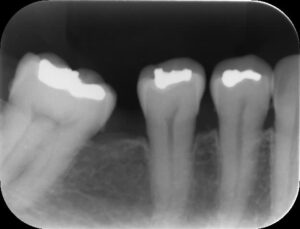

ーアップライト前ー

上のレントゲン写真のように奥歯が手前に傾いてしまっている歯を正しい位置に戻してあげる治療です。